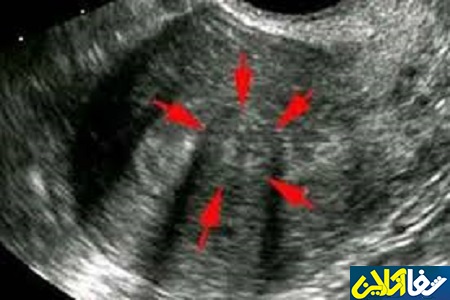

شفاآنلاین>سلامت جنسی>فیبروم رحم با نام علمی «Uterine fibroids» توده‌ای فشرده از عضله است که معمولاً روی دیواره رحم و گاه خارج از آن رشد می‌کند. این توده که در اندازه‌های متفاوت دیده می‌شود، 20تا30درصد زنان را درگیر می‌کند.

به گزارش شفاآنلاین،متخصصان معتقدند این توده‌ها که گاهی به کوچکی یک نخودفرنگی هستند و گاهی هم به اندازه یک گریپ فروت رشد می‌کنند؛ در بیشتر مواقع خوش خیم و قابل درمان هستند اما بی‌توجهی به آن می‌تواند به نازایی، کم خونی و مشکلات خطرناکی منجر شود.